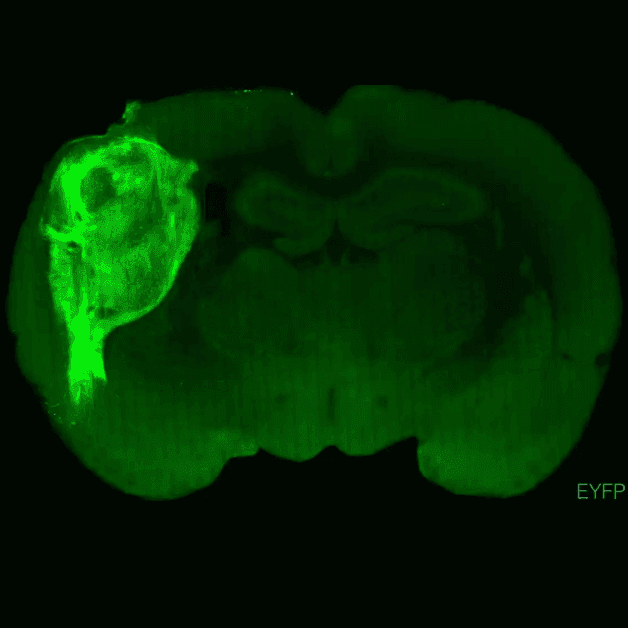

A team of scientists at Stanford University recently transplanted human neurons into rat brains, hoping to open new pathways of research into neuropsychiatric disorders like epilepsy and schizophrenia. But what exactly are these scientists doing? And is it ethical to create these human-rat chimaeras? We explore further with neurogeneticist Dr Azlina Ahmad Annuar, and developmental neurogeneticist Assoc Prof Dr Michael Ling from Universiti Putra Malaysia.

Image Credit: Stanford University/PA